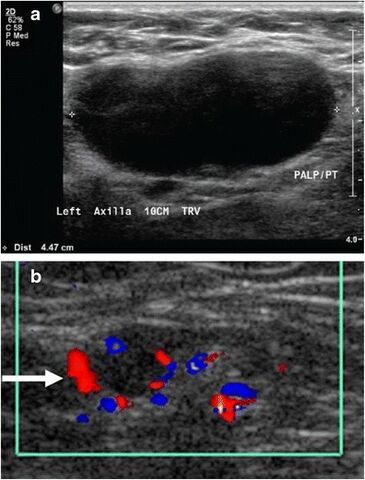

Medical ultrasonography of a soft tissue lump, showing signs of a suspected malignant lymph node:[15]

- Doppler ultrasonography that shows hyperaemic blood flow in the hilum and central cortex and/or abnormal (non-hilar cortical) blood flow

- Increased focal cortical thickness greater than 3 mm

- Absence of the fatty hilum

Doppler ultrasonography can help distinguishing benign from malignant soft tissue lumps.[15] Power Doppler is useful in assessing tendon and joints inflammation such as paratenonitis.[16]